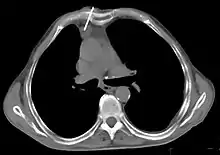

Le scanner thoracique est plus précis que la radiographie thoracique dans le diagnostic des thymomes, en raison d'une plus grande sensibilité envers les masses médiastinales. L'injection de produit de contraste iodé n'est pas forcément nécessaire, mais permet de préciser les rapports du thymome avec les structures vasculaires. Ceci permet à la fois la stadification et de préciser la stratégie chirurgicale lorsqu'elle est envisagée[28].

Les thymomes se présentent comme une masse bien définie du médiastin antérieur, proche du péricarde et dans un plan plus antérieur que les gros vaisseaux intrathoraciques (aorte ascendante et sa crosse, artère pulmonaire, veine cave supérieure). La masse peut être sphérique ou lobulée, mais présente un aspect homogène (plus rarement kystique) qui se réhausse après injection et peut contenir des calcifications[29].

Les critères scanographiques d'envahissement local doivent être recherchés car ils guideront le traitement. D'autre part, l'envahissement scanographique est corrélé au pronostic[30]. L'absence d'un liseré graisseux entre la masse et les vaisseaux, notamment l'aorte et la veine cave supérieure, est un signe d'envahissement local. L'ascension d'une coupole diaphragmatique, comme en radiographie thoracique, est un signe d'envahissement du nerf phrénique[31].

Présentation tomodensitométrique classique d'un thymome à un stade précoce (cercle rouge). À l'arrière, l'aorte, la veine cave supérieure et l'artère pulmonaire sont visibles en coupe.

Scanner injecté, en fenêtre médiastinale, montrant un carcinome thymique envahissant les structures médiastinales :

1 : tumeur hétérogène, aux contours irréguliers, présentant des plages hémorragiques ;

2 : veine cave supérieure ;

3 : tronc artériel brachiocéphalique ;

4 : artères sous-clavière gauche et carotide commune gauche ;

5 : crosse de l'aorte ;

6 : sternum.